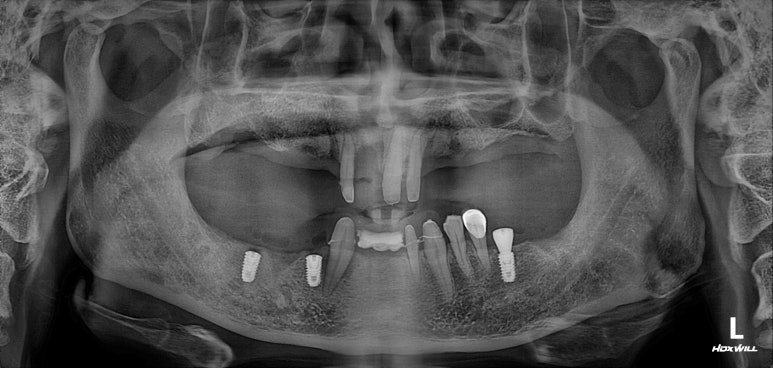

만성치주염으로 흔들리는 어금니를 수 년전 발치하고 방치되어 앞니까지 뽑게된 50대 남자 환자의 케이스를 소개해드리겠습니다. 생각보다 많지 않은 개수의 임플란트와 앞니는 지르코니아 브릿지로 제작하여 아주 예쁘고 기능성있게 치료해드렸던 환자분입니다.

몇 년전 만성치주염으로 흔들리는 어금니를 뽑았어요.

임플란트 치료를 받지 않았더니 앞니도 흔들립니다.

딱 봐도 치아가 많이 없으신 50대 남자 환자분입니다.

어떻게 그 동안 식사를 하셨는지 단번에 걱정이 되었던 분.. 개원 후 얼마 되지 않아 방문해셨던 분이라 더욱 기억에 남는 분입니다.

보통 만성치주염이 시작되면, 흔히 맨 뒤 어금니부터 상실하게 됩니다.

그 이유는 비교적 간단합니다. 맨 뒤 어금니가 가장 닦기 힘든 자리에 있기 때문이죠. 대부분 소홀해진 구강위생관리로 인해 생긴 치석 때문에 시작된 만성치주염으로 다수의 치아를 잃곤 하십니다.

사실 보고 있자니 마음이 심란합니다.

큰 어금니는 한개 밖에 남지 않았고, 그나마 작은 어금니도 여러개 소실되어 있네요.

아래 앞니도 없어졌고.....